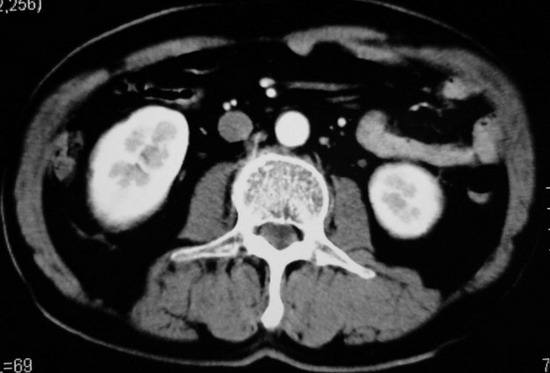

以下是引用杀毒软件在2008-11-17 19:15:00的发言:[br]考虑------右肾癌合并肾静脉---同侧肾上腺受侵可能性大

以下是引用zjzjr在2008-11-17 20:45:00的发言:[br]考虑------右肾癌合并肾静脉---同侧肾上腺受侵可能性大及腹膜后淋巴结转移.